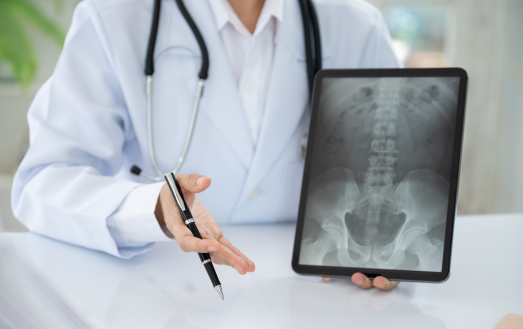

En trygg väg till diagnos genom bilddiagnostik

Som legitimerad kiropraktor vägleder jag dig från klinisk misstanke till tolkning av resultat.

Som en del av din utredning på Kroppia gör vi en noggrann klinisk bedömning av om bilddiagnostik är nödvändig för att fastställa rätt diagnos eller säkerställa att behandling kan ske tryggt.

Vi börjar alltid med en grundlig klinisk funktionsanalys. Bilddiagnostik används som ett precisionsverktyg när vi behöver bekräfta fynd eller utesluta bakomliggande orsaker som inte syns vid en manuell undersökning.

Vi går igenom dina röntgen- eller MR-svar tillsammans. Det viktigaste är hur bilderna korrelerar med din biomekaniska status, så att vi kan utforma en träffsäker behandlingsplan.

Tolkning & Åtgärd